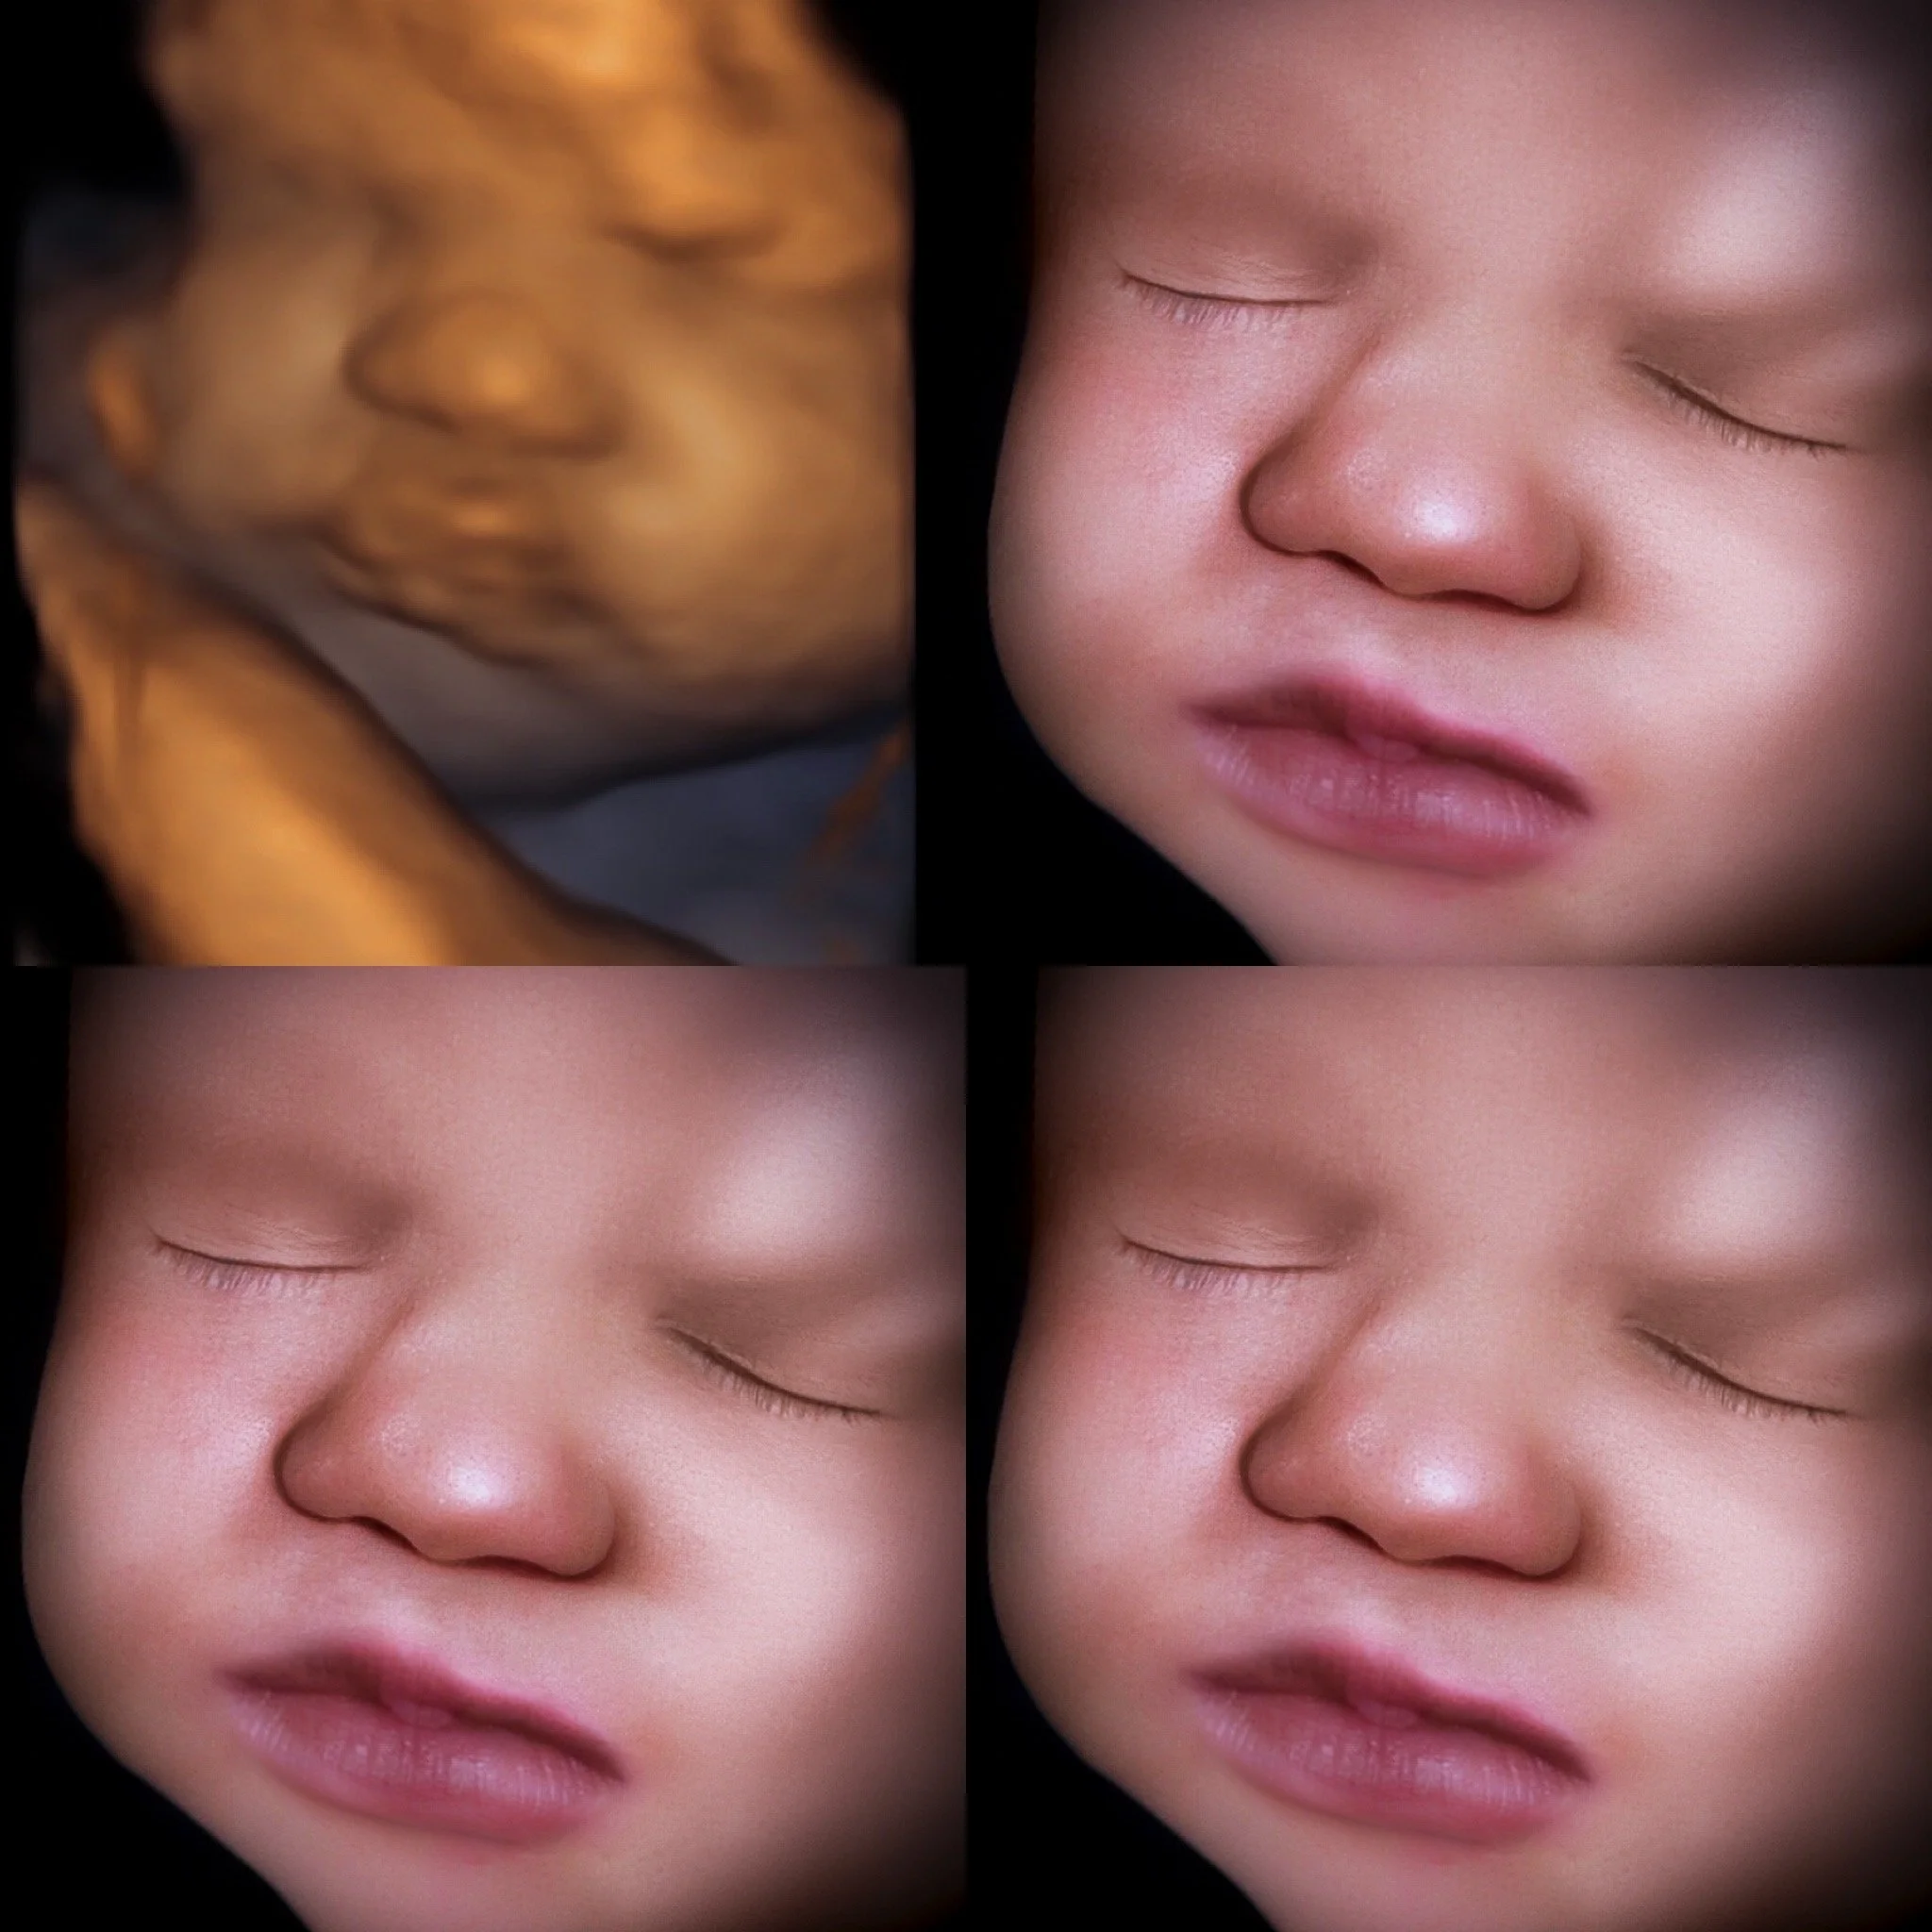

Saturday Appointments

Friday & Saturday appointments available for gender reveals & 3D/4D ultrasounds!